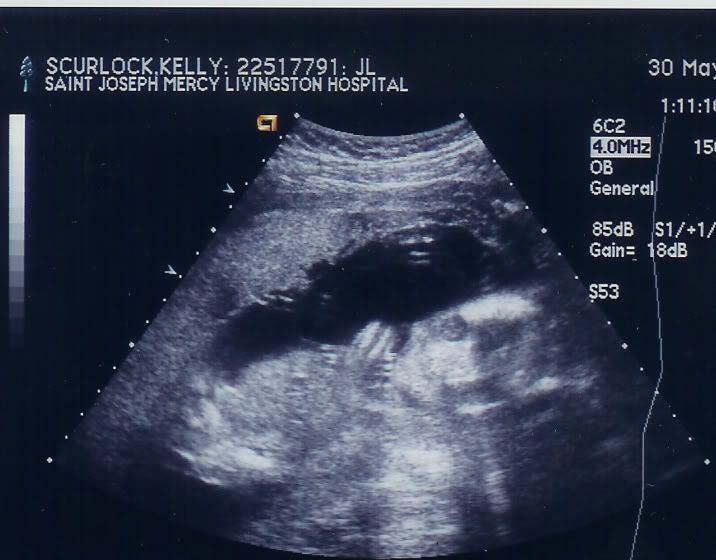

i had my ultrasound today...it's a boy.....hahaha hi saw it's lil ******

it was pretty cool. they messured all the bones, and i saw its brain....here's the ultrasound pics....he he he its waving in one of them...i think it looks like a lil alien.

speede- yeah those are his eyes....super creapy huh? his legs are there you just can't see them. b/c of where she had the hand piece to the ultrasound machine.